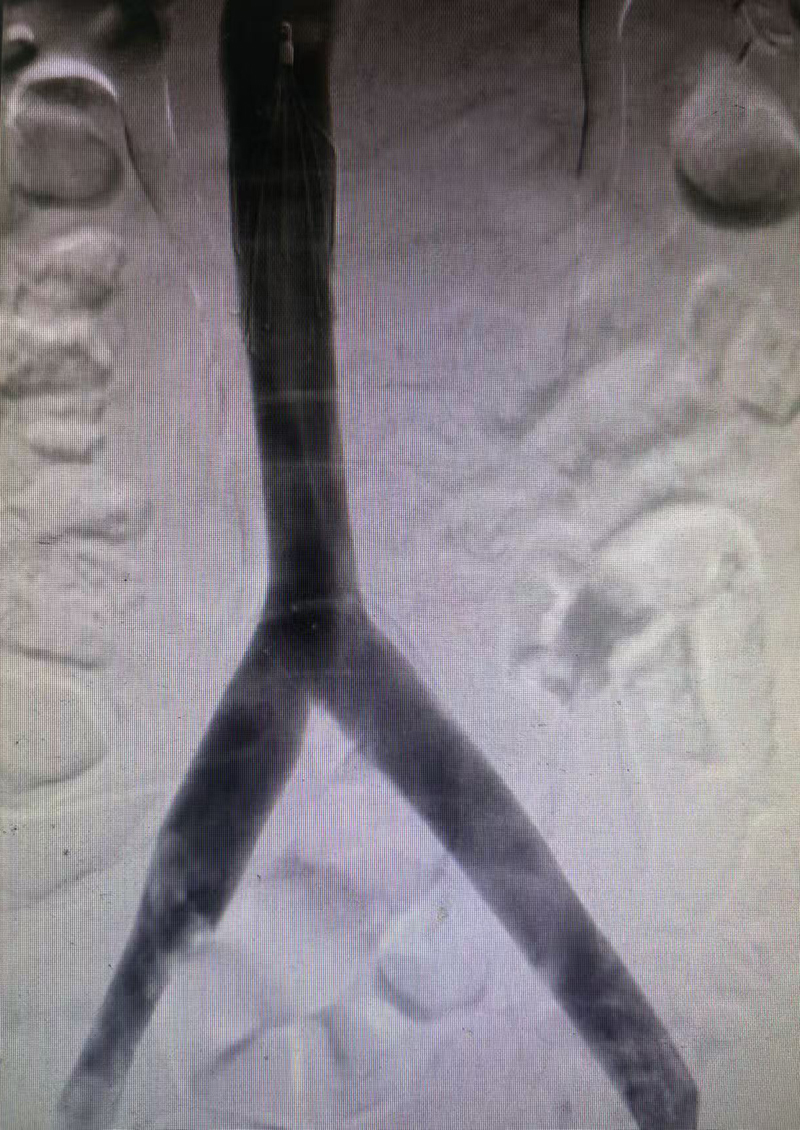

3.髂静脉支架植入——解除“先天枷锁”:血栓清除后,造影揭示了疾病的根本原因——患者左侧髂总静脉受右侧髂动脉及腰椎压迫明显,管腔狭窄超过70%。这正是血栓发作的“元凶”。术者精准测量病变长度与直径后,在髂静脉狭窄段精准释放支架,原本塌陷的静脉管腔即刻恢复通畅。